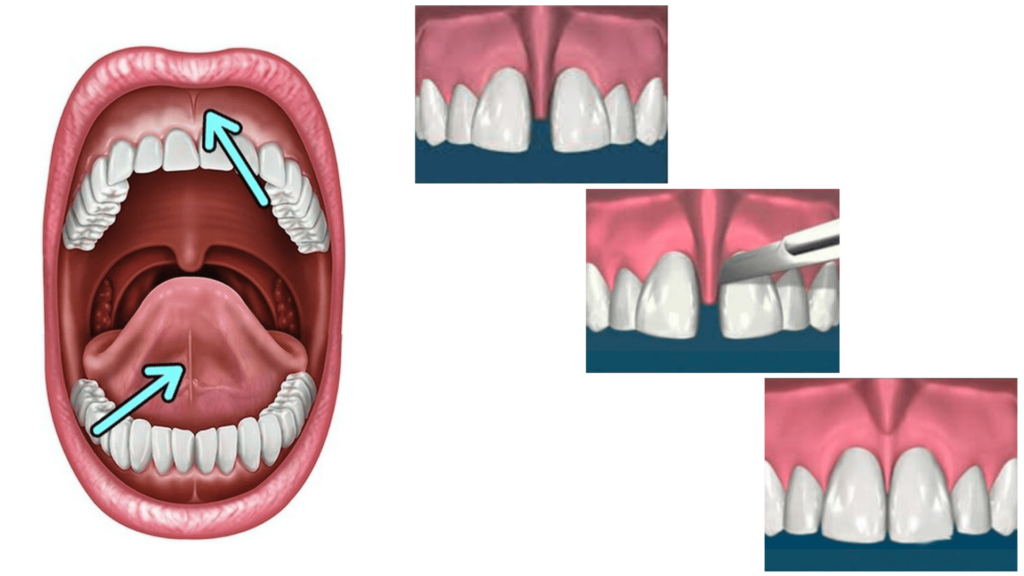

FRENULEKTOMIJA

Frenulektomija je oralno-kirurški zahvat kojim se oslobađa frenulum – resica koja se nalazi ispod gornje usne ili ispod jezika.

Frenulum u donjoj čeljusti može ograničavati pokretljivost jezika i otežavati govor, dok u gornjoj čeljusti može uzrokovati razmak između prednjih zuba (dijastemu) ili povlačenje zubnog mesa.

Zahvat je jednostavan, bezbolan i traje kratko.

Zahvat se radi pod lokalnom anestezijom, a oporavak je brz i bezbolan.